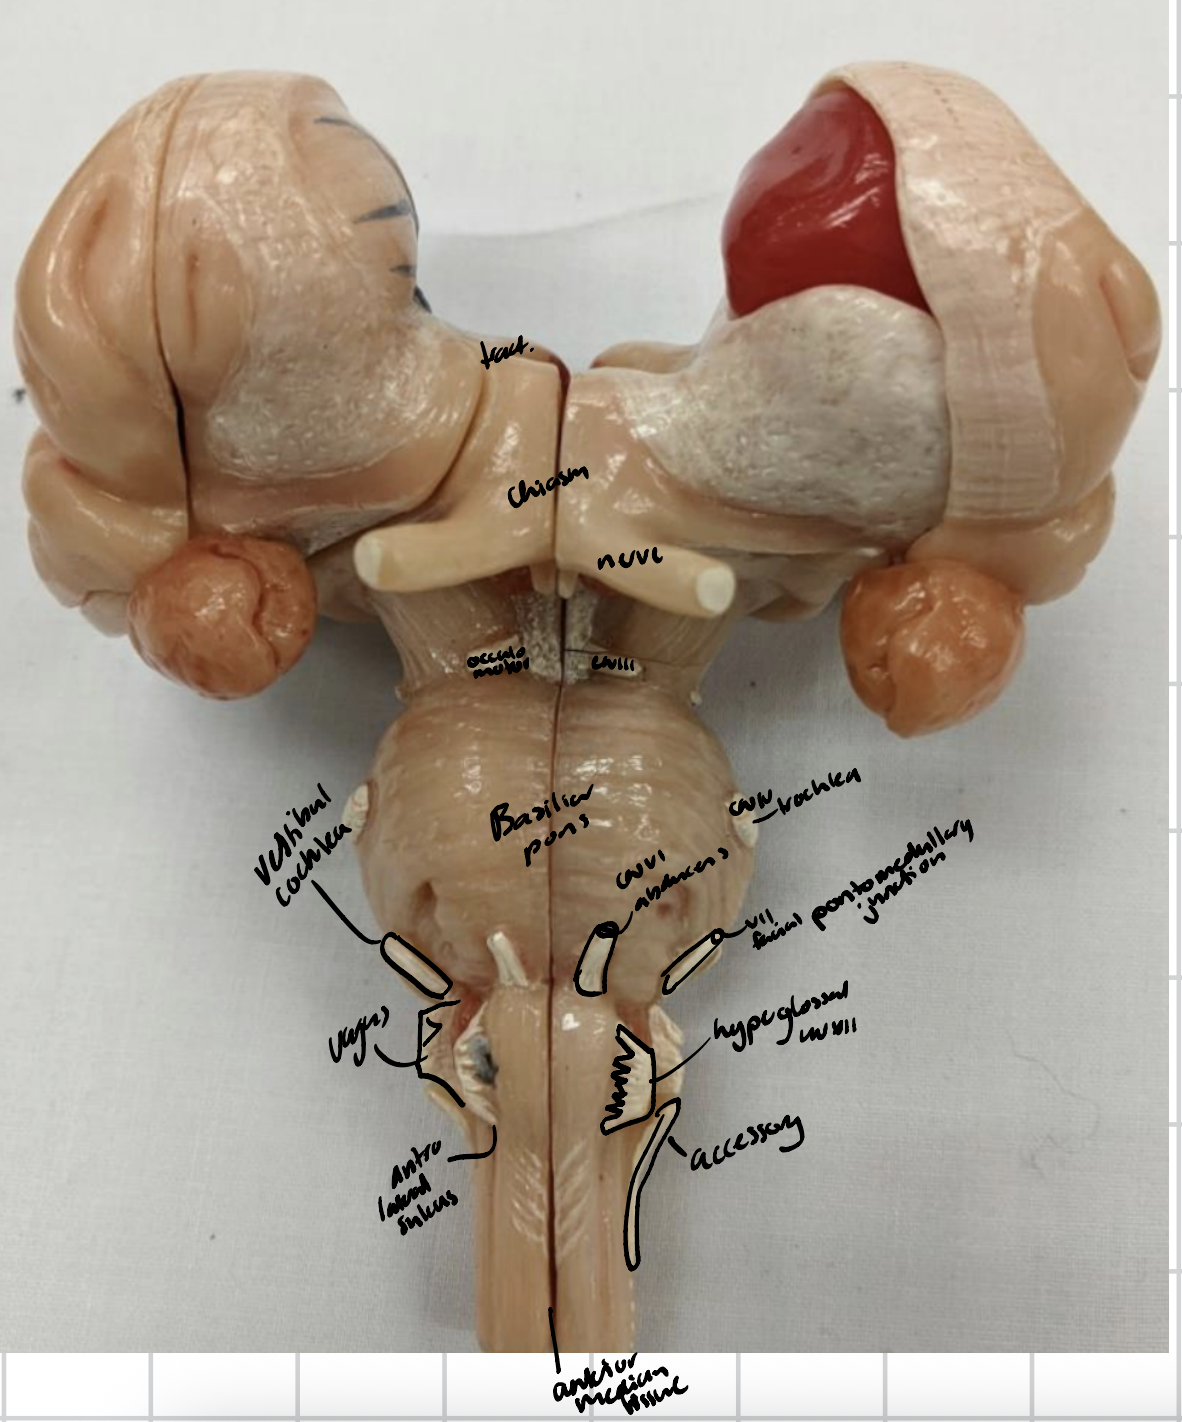

Optic chiasm

The anterior, posterior and lateral semicircular canals

Ampulae

Oval window

Base of the stapes

Vestibule

Cochlea

Cochlea division of CNVIII

Optic chiasm

Mammillary bodies

Pathway of CNI

Cranial Nerves